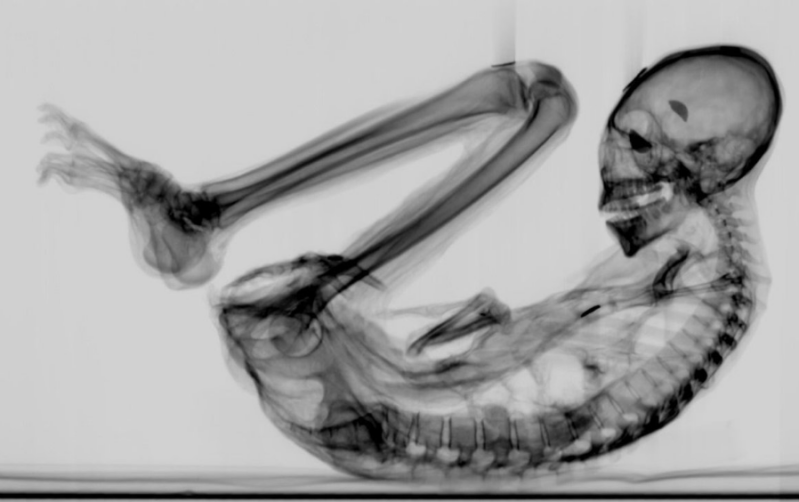

Nazca Mummies DNA Update: The 30% Unknown That Never Went Away

Updated DNA analysis of the Nazca mummies is quietly circulating again. Around 30 percent of the sequences from Maria and Victoria remain unidentified, with non-concordant markers that never aligned with standard human evolution models. This data was not disproven, it was set aside, and its return now suggests unfinished questions are being reopened. Learn More